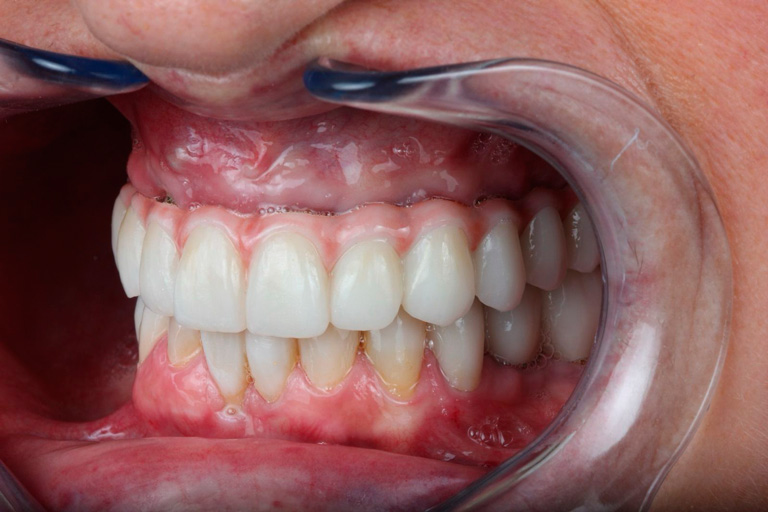

Odontología Estética. Coronas

BeforeAfter